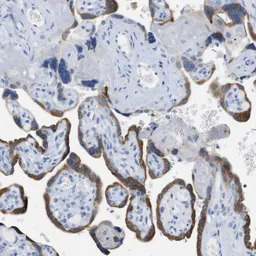

Paraffin-embedded human placenta tissue immunostained with GTX60972

Immunohistochemical staining of a formalin-fixed, paraffin-embedded placental tissue with GTX60972